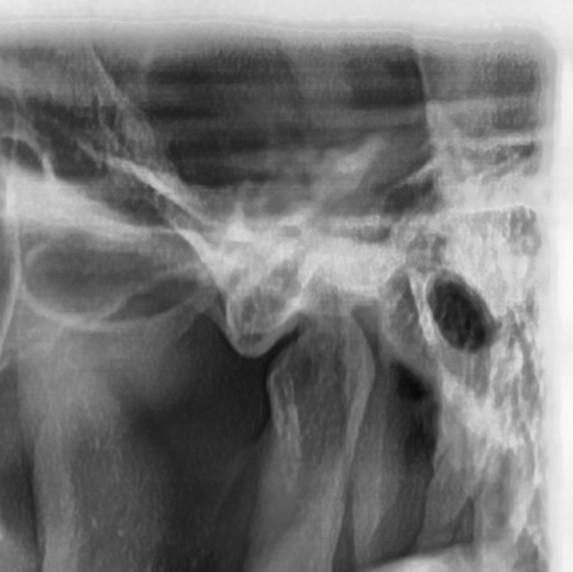

씹을 때 턱이 아파요 턱 과두 한 번 봐주세요

약간 단단한 거 먹을 때 턱이 아픈데요 지금 현재 상태가 병원에가서 치료 받아야 할 정도인가요?

몇 달 전부터 증상이 시작 됐는데 확인 한번 부탁드립니다

왼쪽 턱관절의 condyle 모양이 다소 각이져 있긴 한데 심한 턱관절염으로 보이진 않습니다. 딱딱한 음식 피하시고, 턱 마사지 해주세요 증상이 그래도 지속되면 구강내과 가보세요